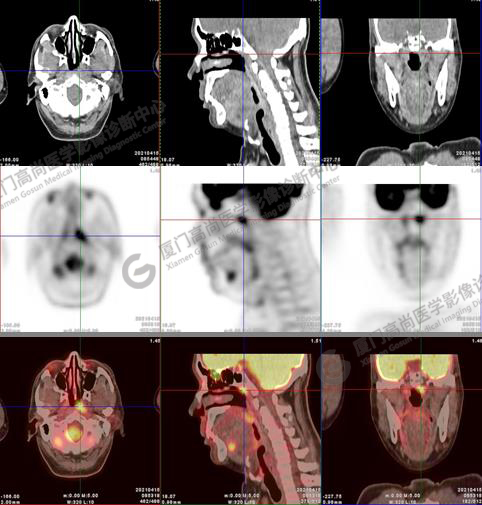

圖1:PET/CT全身圖像

圖2:雙側(cè)頸部多發(fā)增大淋巴結(jié),代謝不同程度增高,考慮為轉(zhuǎn)移。

圖6-9:鼻咽左側(cè)壁增厚,代謝異常增高,考慮為鼻咽癌